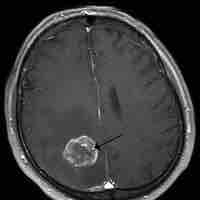

Brain Tumors

A brain tumor is a pathological abnormal growth of cells in the brain.